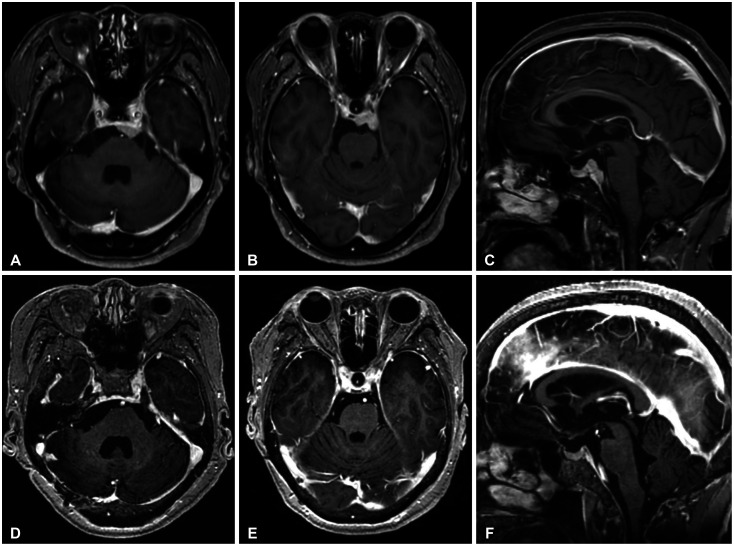

We report complete remission of dural-based leptomeningeal metastasis (LM) in an 80-year-old female patient with non-small cell lung cancer (NSCLC) by osimertinib. She was diagnosed with NSCLC (adenocarcinoma, T4N3M1a) 8 years ago. Mutation analysis of biopsied tissue revealed exon 19 deletion positive, and gefitinib was prescribed. Follow-up chest CT showed a radiological response, and whole-body positron emission tomography 3 years later revealed the disappearance of the previous high-uptake lesions. The medication was continued for maintenance but stopped 4 years later due to intolerable dermatitis. Two years after discontinuing chemotherapy, the patient had a gait disturbance, and brain MRI revealed a right cerebellar mass (diameter [d]=3 cm) with peritumoral edema, compatible with solitary brain metastasis. Retromastoid suboccipital craniotomy and gross total removal of the dura-attached lesion were performed. As the systemic cancer status evaluation revealed no radiological cancer lesion, only tumor bed radiation therapy was given (4,000 cGy/10 fractions) without re-introducing gefitinib. She was followed with a brain MRI at 6-month intervals, and a brain MRI 2 years postoperatively revealed a dural-based extra-axial mass in the left prepontine cistern (d=2.2 cm). Serial cerebrospinal fluid (CSF) cytology was positive for cancer cells. Upon LM diagnosis, the third-generation receptor tyrosine kinase inhibitor osimertinib was given. Two-month follow-up CSF cytology and five consecutive tests over 14 months demonstrated negative conversion. Five-month follow-up brain MRI revealed near complete remission of dural-based LM, and the response was maintained until the 13-month follow-up brain MRI.

我们报告了一位80岁的女性非小细胞肺癌(NSCLC)患者通过奥希替尼治疗硬脑膜脑膜转移(LM)完全缓解的病例。她在 8 年前被诊断为非小细胞肺癌(腺癌,T4N3M1a)。活检组织的突变分析显示 19 号外显子缺失为阳性,医生给她开了吉非替尼。随访的胸部 CT 显示有放射反应,3 年后的全身正电子发射断层扫描显示之前的高吸收病灶消失了。患者继续接受药物维持治疗,但 4 年后因无法忍受皮炎而停药。停止化疗两年后,患者出现步态障碍,脑部核磁共振检查发现右侧小脑肿块(直径[d]=3厘米),瘤周水肿,符合单发脑转移。患者接受了后枕骨下开颅手术,彻底切除了硬膜外病灶。由于全身癌症状况评估未发现放射性癌症病灶,因此只进行了肿瘤床放疗(4,000 cGy/10次分次),未再次使用吉非替尼。术后两年的脑部核磁共振检查显示,左侧桥脑前囊有硬膜外肿块(d=2.2 厘米)。连续的脑脊液(CSF)细胞学检查显示癌细胞阳性。LM确诊后,患者接受了第三代受体酪氨酸激酶抑制剂osimertinib治疗。两个月的CSF细胞学随访和14个月的连续五次检测均显示阴性。五个月的脑磁共振随访显示,硬脑膜LM几乎完全缓解,这种反应一直维持到13个月的脑磁共振随访。